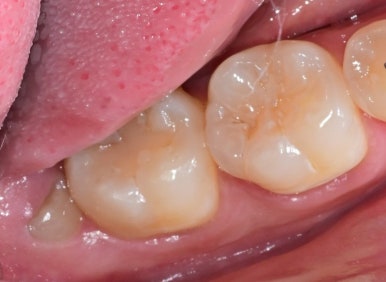

📌 사랑니 발치 실제 사례

최근 내원한 20대 여성 환자분은

좌측 아래 사랑니 부위에 통증이 반복되어 내원하셨습니다.

| 발치 전 | 발치 후 |

CT 검사 결과,

사랑니는 똑바로 있었지만 맹출 공간이 부족해

기능적 활용이 어려운 상태였고,

결국 발치를 결정하셨습니다.

수술은 국소마취로 약 10분 만에 마무리되었고,

현재는 빠르게 회복 중입니다 😊